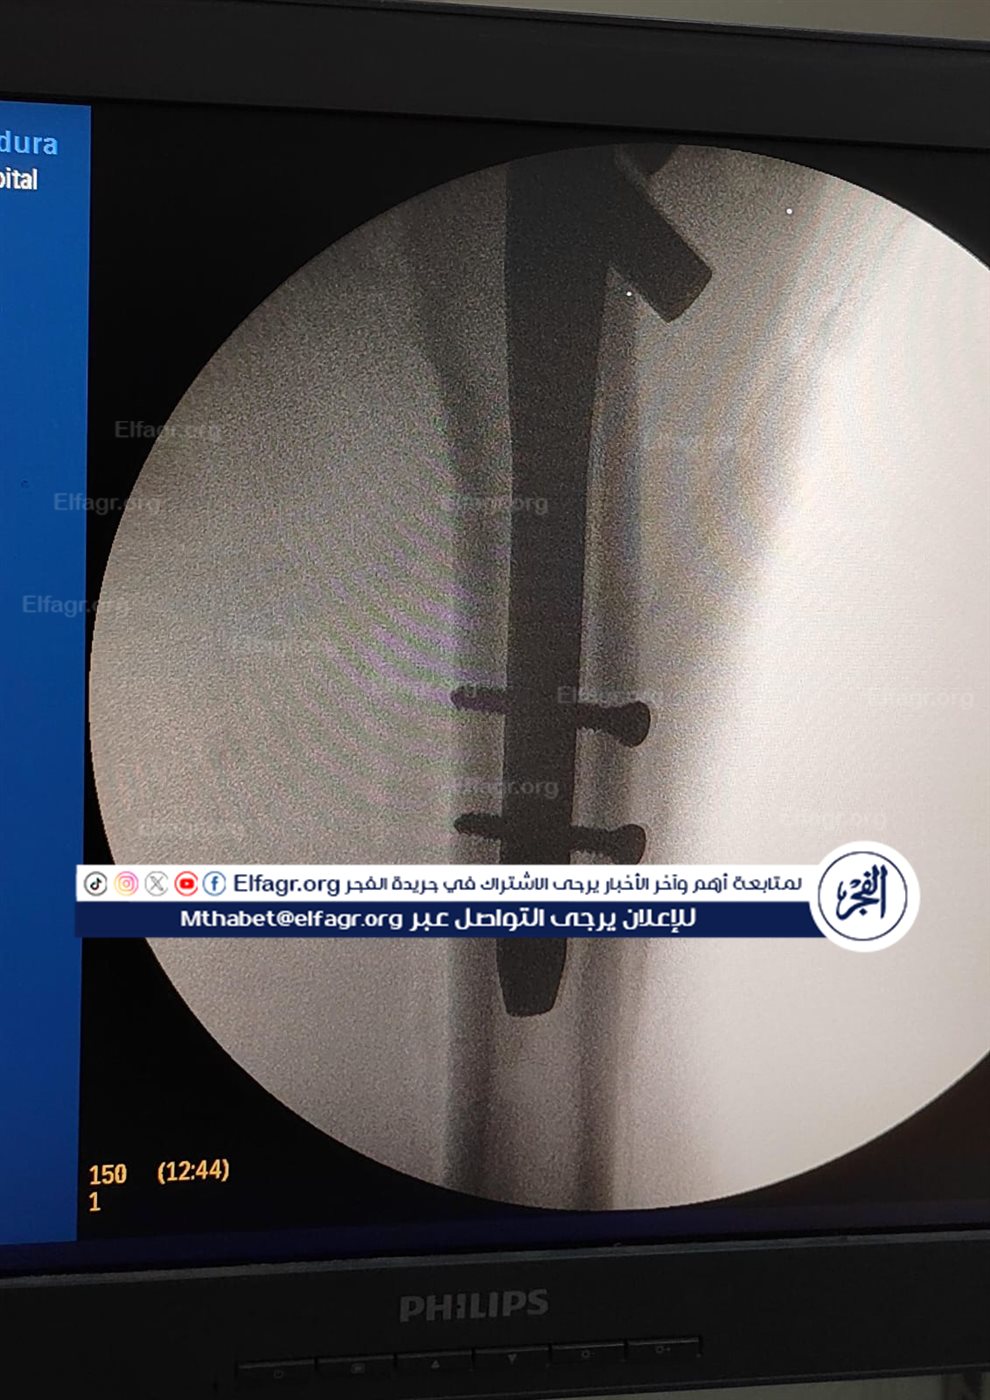

شملت العمليات تركيب كويرات بالرضفة اليسرى لمريض، وكذلك تركيب مسمار نخاعي بالفخذ الأيسر لمريض آخر، حيث تمت العمليتان بدقة عالية وباستخدام تقنيات حديثة ساهمت في تحقيق النتائج المرجوة.

جانب من الجراحة